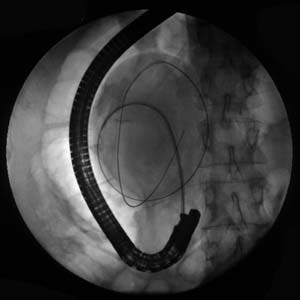

Рентгеноскопия + эндоскопия = ЭРХПГ.

Рис. 6. Большая киста головки поджелудочной железы. Дренирование кисты внутренним дренажем через дуоденоскоп ТJF-30.